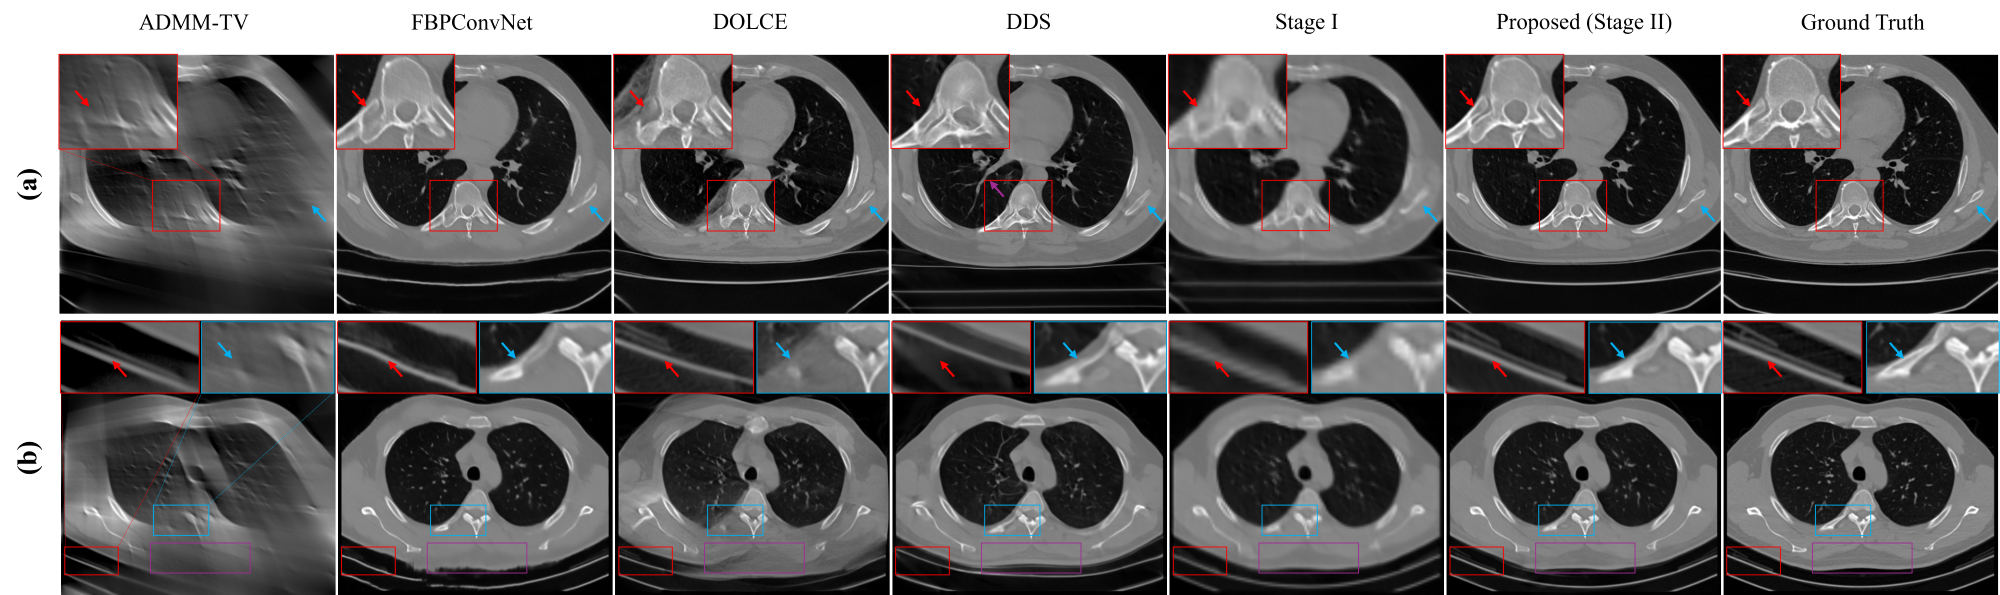

To evaluate the generalizability of the proposed method, we conduct two out-of-distribution experiments on CTRATE: one using fan-beam CT projection at a 75° angular range, which was not included in the training set, and the other with 45° parallel-beam projections, whose angle and geometry do not appear during training. Results of the first experiment are presented in Fig.5. In high-contrast bony regions (Fig.5 (a)), FBPConvNet reconstructs the gross structure of the thoracic vertebrae, but fails to resolve the interspaces between the vertebrae and ribs (red arrows), and degrades in severely truncated areas (blue arrow). Due to domain shift between the training and testing distributions, DOLCE introduces ground-glass-like artifacts above the ribs, which may lead to misdiagnosis. DDS improves edge sharpness and bone contrast but generates artificial textures, as highlighted by purple arrow in Fig.5 (a). Our method provides sharp vertebral reconstructions and clear separation between vertebrae and ribs with minimal hallucinations. In soft-tissue evaluation (Fig.5 (b)), both FBPConvNet and DOLCE fail to recover clean anatomical contours, while DDS offers sharper edges that still deviate from the reference. The proposed method achieves the most faithful visual appearance, especially in missing-data regions, where it reconstructs realistic structure and soft-tissue contrast closely aligned with the ground truth.

To further assess the generalizability, we test on real cardiac CT data from a GE scanner. Due to differences in hardware, protocols, and patient populations, the GE dataset introduces a noticeable domain shift relative to CTRATE. To preserve the signal integrity, no nonlinear post-processing is applied to the raw sinograms, further amplifying the training-testing gap.

Fig. 7 presents the clinical reconstruction results. As expected, traditional iterative methods such as ADMM-TV are relatively robust to data distribution shifts, producing results with consistent visual characteristics. In contrast, FBPConvNet suffers from substantial pixel bias, leading to visible global gray-level shifts. Consequently, its SSIM, RMSE, and PSNR degrade significantly, and even fall below ADMM-TV. Nevertheless, since FBPConvNet preserves global structural integrity to some extent, its nMI and PCC remain relatively high. DOLCE, as a supervised model, benefits from an explicit data consistency term that partially mitigates global intensity drift. However, in the 90° limited-angle setting, DOLCE fails to suppress limited-angle artifacts, unlike on CTRATE data (e.g., Fig.4(b)). DDS, which integrates unsupervised learning with data consistency, partially addresses the artifact issue in 90° scan. Building upon this, our method further leverages metadata prior during reconstruction. As a result, it consistently outperforms all baselines in structural fidelity, intensity restoration, and artifact suppression as supported by the quantitative metrics in Table 4.

However, these models are not immune to domain shifts in non-patient regions, notably medical bed structures, which vary across scanners. A likely reason is the mismatch between the diversity of patient anatomy and the homogeneity of imaging environments in the training set. For example, CTRATE predominantly contains a double-layered supports contrary to our clinical dataset. Consequently, as observed in Fig. 7 (b), both DDS and our method tend to hallucinate a double-layered bed structure at 90° angle, despite its absence in the ground truth. To address this, we perform a lightweight domain adaptation by fine-tuning the model on two target-domain patients. After 200 iterations per stage, the adapted model successfully eliminates the bed hallucination artifact, as illustrated in Fig. 7. This result suggests that few-shot fine-tuning can effectively mitigate such distribution mismatches.